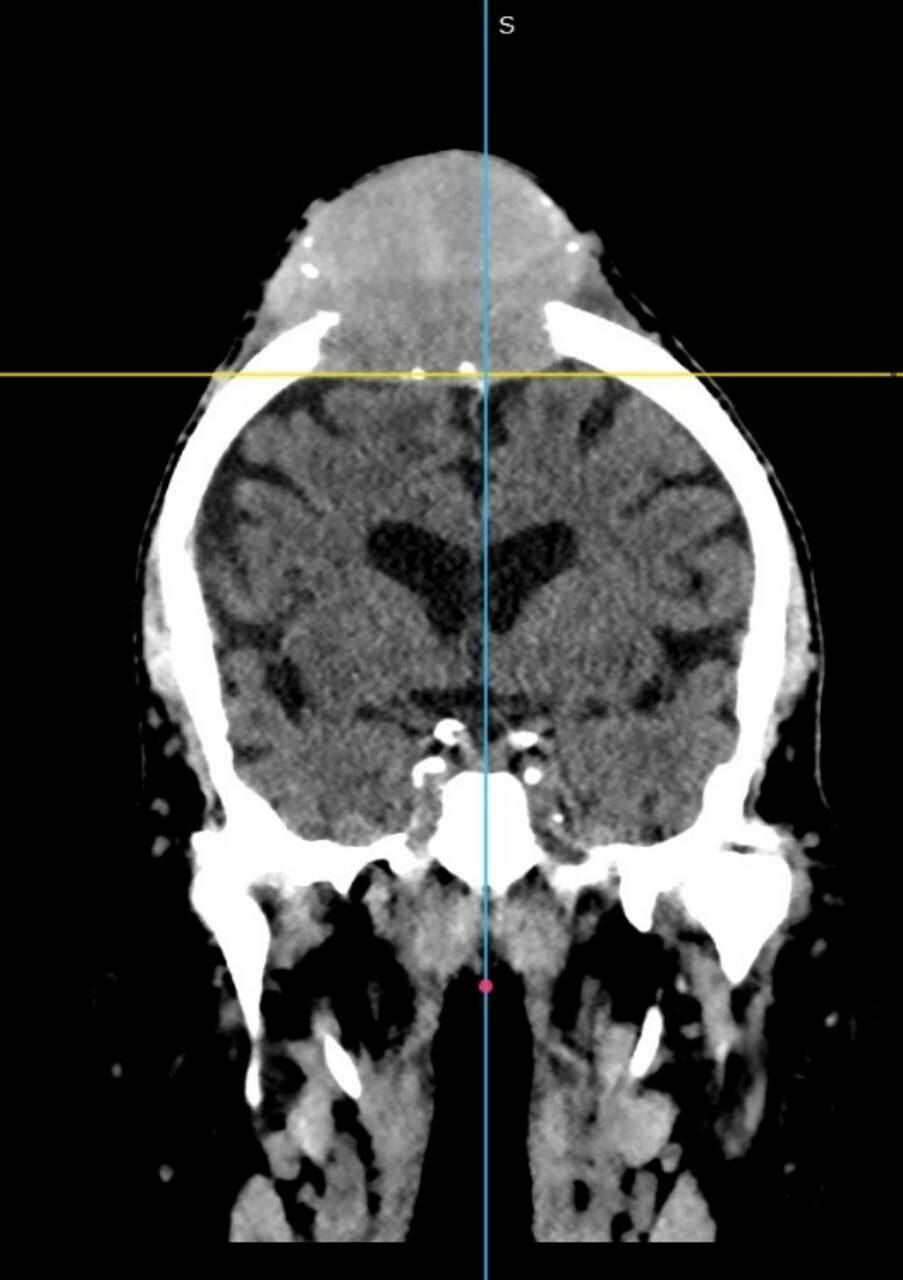

11 ноября в Республиканскую клиническую больницу Татарстана поступил 78-летний мужчина с постоянно растущим образованием на голове. Об этом «Татар-информу» рассказали в пресс-службе клиники.

В 2016 году мужчина перенес операцию по поводу рака правой почки, наблюдался у онколога. В декабре прошлого года заметил, что на голове растет шишка.

«По направлению из ЦРБ прошел обследования в РКОД, откуда его направили на удаление образования к нам. 13 ноября нейрохирурги РКБ Татарстана удалили образование и сделали пластику титановой сеткой», – объяснили в РКБ Татарстана.

Гистология показала, что в голове вырос метастаз рака почки.